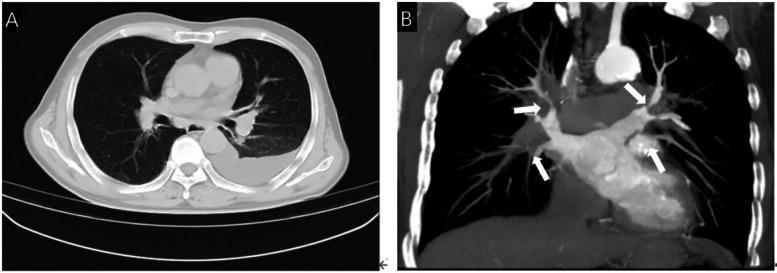

An elderly male patient presented with intermittent chest tightness, shortness of breath, cough, and large pleural effusion. He was diagnosed with fibrosing mediastinitis through echocardiography, chest CT, and inflammatory indicators. Contrast-enhanced CT and selective angiography showed severe stenosis of multiple branches of bilateral pulmonary veins. The patient is considered to have pulmonary vein stenosis caused by FM, and for further treatment, we performed two interventional therapies at different times. After two operations, the stenosis of bilateral multiple pulmonary veins in this patient has been relieved. Additionally, we also discovered that for pulmonary vein stenosis caused by FM, stent implantation is more effective than balloon dilation.

一名老年男性患者出现间歇性胸闷、气短、咳嗽及大量胸腔积液。通过超声心动图、胸部CT及炎症指标检查,他被诊断为纤维性纵隔炎。增强CT及选择性血管造影显示双侧肺静脉多个分支严重狭窄。该患者被认为患有由纤维性纵隔炎导致的肺静脉狭窄,为进一步治疗,我们在不同时间进行了两次介入治疗。两次手术后,该患者双侧多条肺静脉的狭窄情况得到缓解。此外,我们还发现,对于由纤维性纵隔炎导致的肺静脉狭窄,支架植入比球囊扩张更有效。